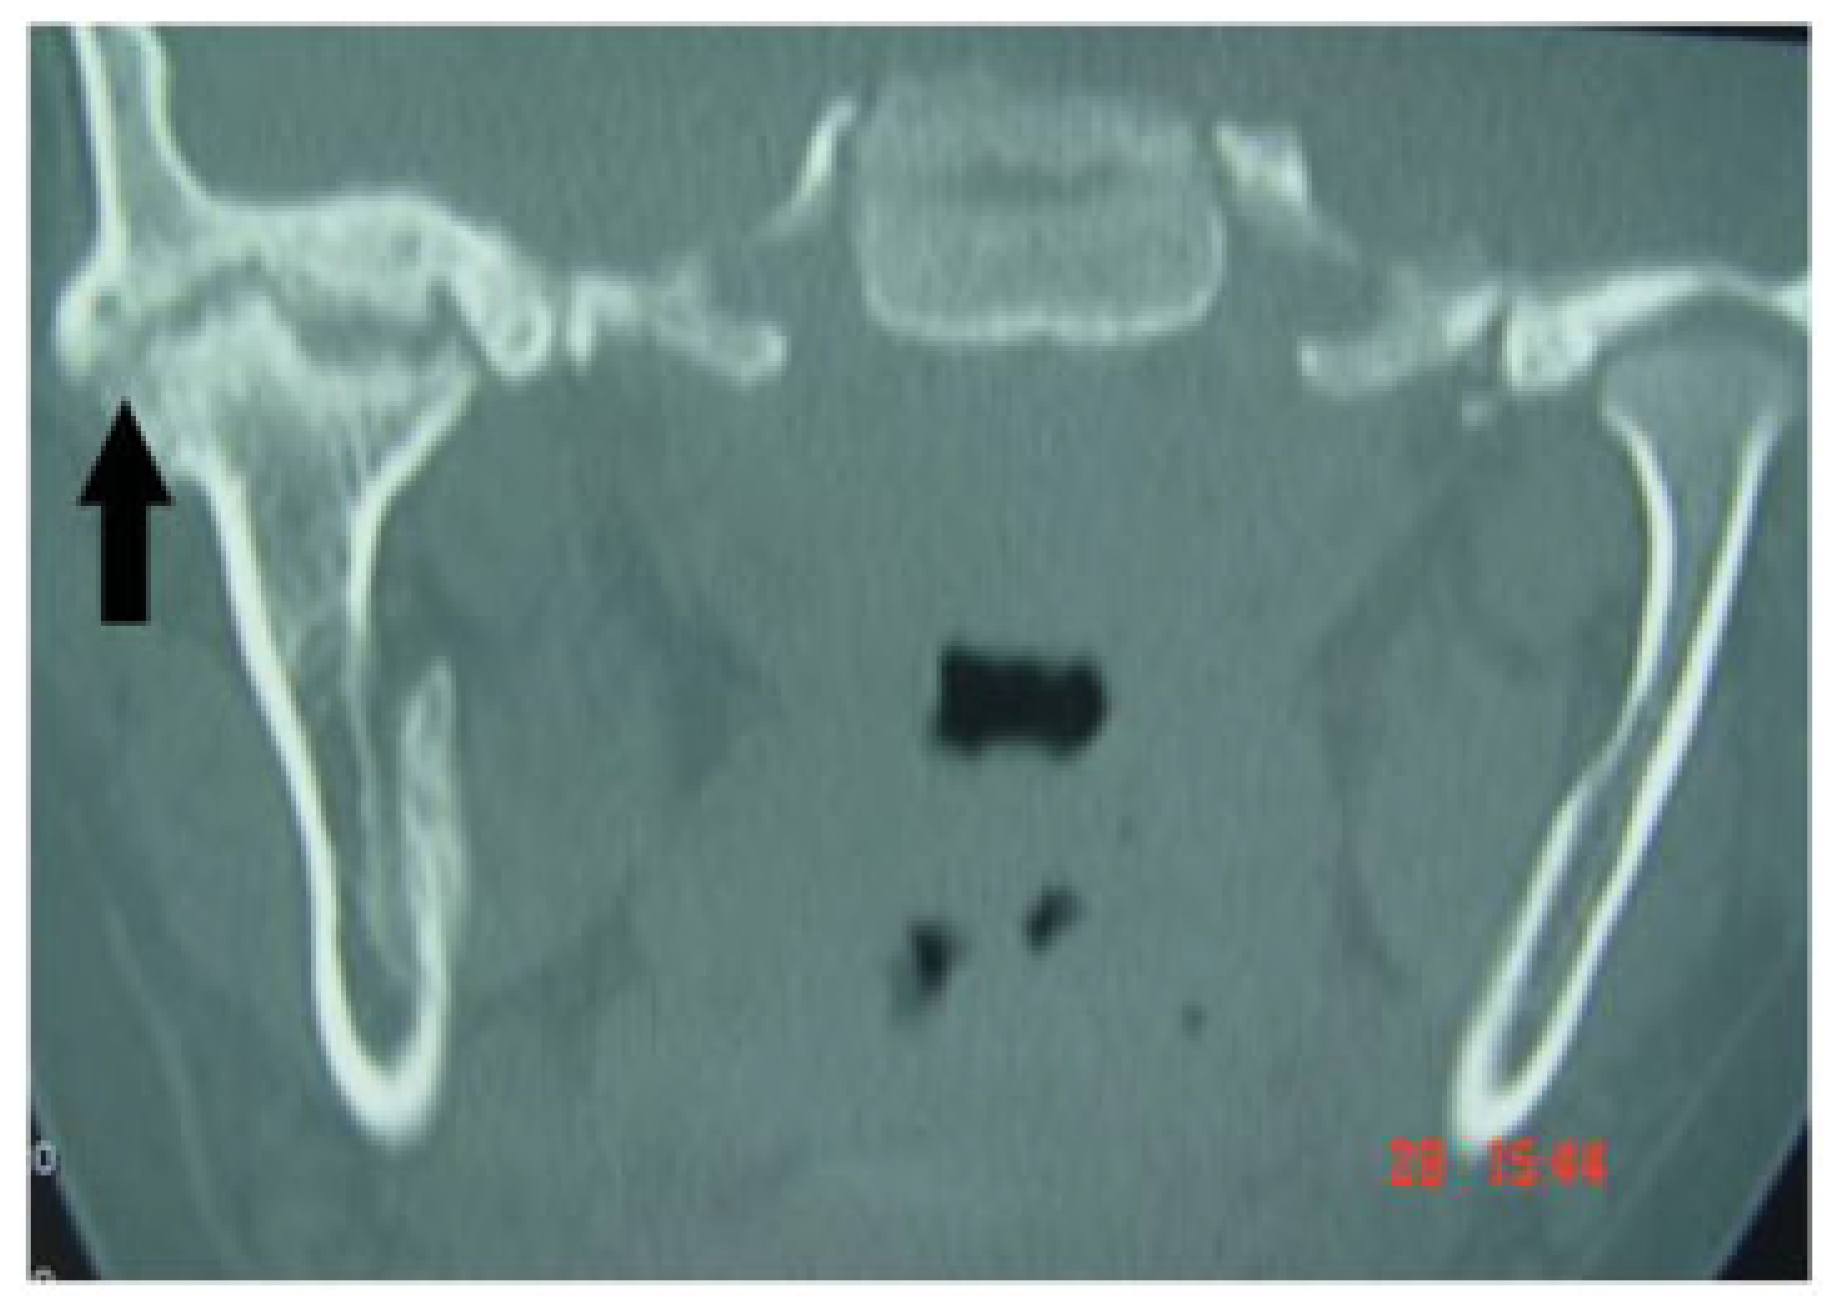

A computed tomography scan showed a mass of bone in the right TMJ region (Figure 3). The fractured mandibular condyle had ankylosed with the skull base. Functional difficulties arose because the articulation at the right TMJ was restricted.

Figure 3. Computed tomography scan showing ankylosed right temporomandibular joint (black arrow).